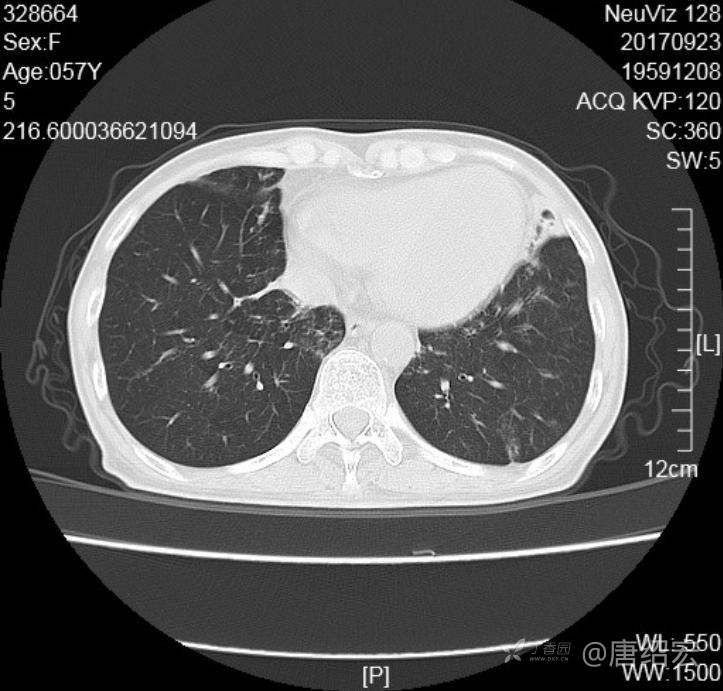

中年女性满肺树芽征还有支气管扩张,考虑什么疾病?

女,57岁,

主诉:发热、咳嗽、咯黄痰,胸闷3天入院。